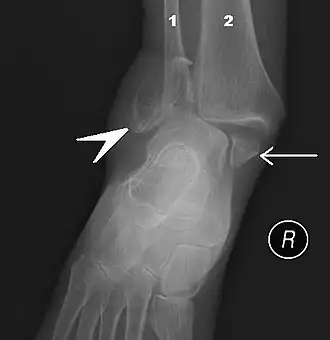

![]() Fractura en ambos lados del tobillo con dislocación vista en radiografía anteroposterior. (1) fíbula, (2) tibia, (flecha) maléolo medial, (cabeza de flecha) maléolo lateral | ||